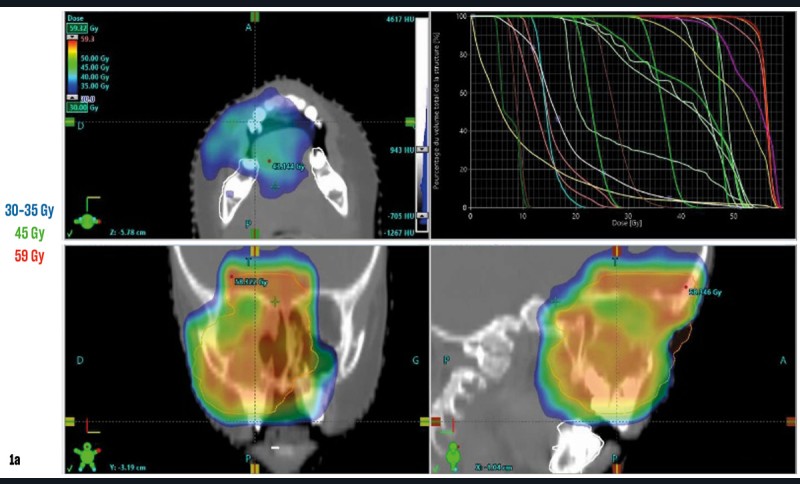

Une jeune patiente âgée de 15 ans, accompagnée de ses parents, est adressée au Centre de Compétences des Maladies Rares Orales et Dentaires (O-Rares) des Hospices Civils de Lyon pour une réhabilitation bucco-dentaire globale. Elle présente un antécédent de sarcome d’Ewing au niveau du sinus maxillaire droit diagnostiqué à l’âge de 3 ans et demi. Ce dernier a été traité par chimiothérapie préchirurgicale, chirurgie d’exérèse, chimiothérapie post-chirurgicale et radiothérapie (dose inférieure à 60 Gy au niveau du site tumoral [fig. 1a et b]). Plus récemment, la patiente a également dû être hospitalisée pour une épistaxis massive à la suite d’une nasofibroscopie ayant nécessité une cautérisation de l’artère sphéno-palatine droite. Sur le plan général, elle présente également un traitement hormonal pour un retard de croissance.